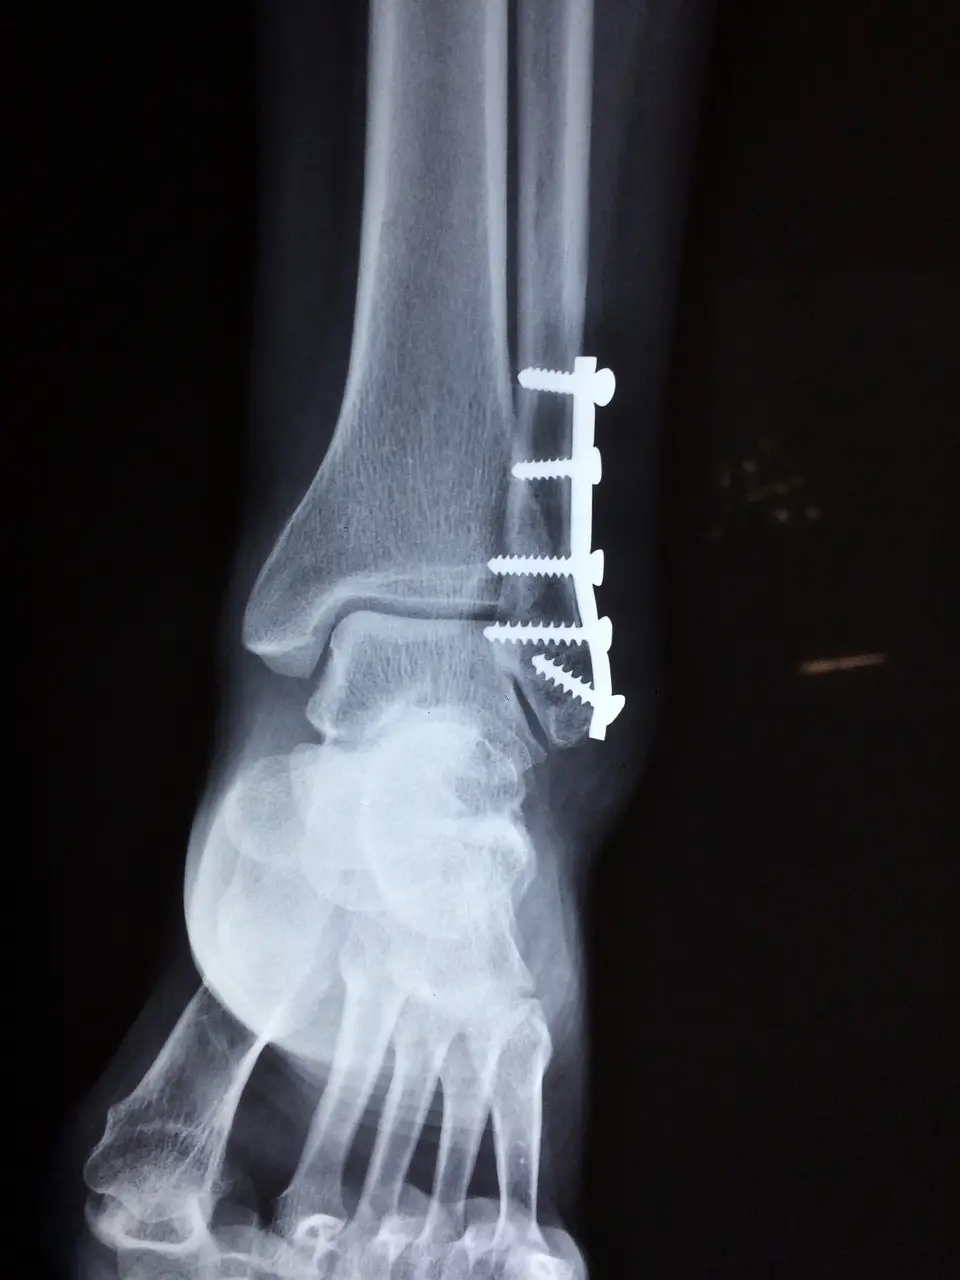

교통사고가 나게 되면 가벼운 찰과상부터 골절, 심한 경우 수술을 해야 하는 상황이 생길 수 있습니다. 이때 모든 치료비는 보험사가 책임지며 교통사고로 인해 신체적 손상이 생긴 경우 보험사는 해당 치료를 완벽히 받을 수 있도록 지원합니다.